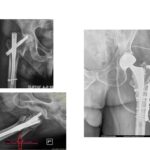

Στις εικόνα 11 και εικόνα 12 ημιαρθροπλαστική AMIS για υποκεφαλικό κάταγμα ισχίου, από προσωπικό αρχείο

Χωρίς ικανή εμπειρία, επιπλοκές μπορεί να συμβούν: στην εικόνα 13, στην αριστερή πλευρά ημιαρθροπλαστική AMIS στην οποία τοποθετήθηκε ολόκληρος ο στυλεός του μηριαίου εκτός του αυλού. Ο ασθενής κινητοποιήθηκε την επομένη με αφόρητο πόνο σε εξάρθρημα. Όσο κι αν φαίνεται απίθανο, είναι μια επιπλοκή που μπορεί να συμβεί σε μη έμπειρα χέρια. Δεξιά στην εικόνα φαίνεται ο ορθός τρόπος τοποθέτησης του στυλεού.